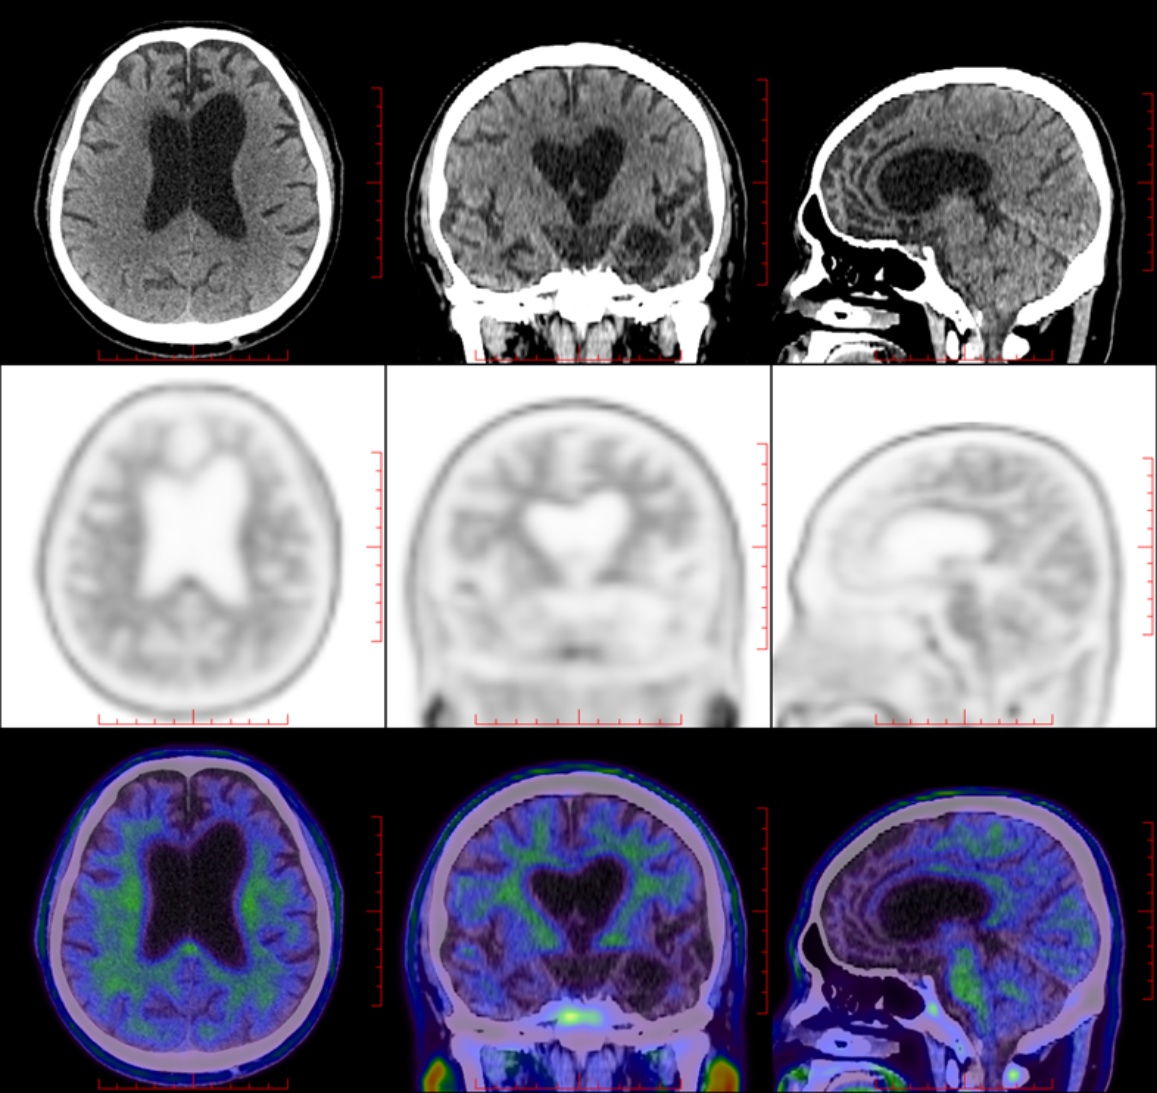

PET-CT:大脑皮质β淀粉样蛋白(Aβ)未见明显沉积;双侧大脑半球多发皮质代谢减低,以左侧额颞叶为著;符合额颞叶痴呆影像学表现(图3图4)。

Figure 4. The glucose metabolism in both the bilateral frontal and temporal lobes, insula, and anterior cingulate gyrus was significantly reduced

4. 双侧额颞叶、岛叶及前扣带回葡萄糖代谢显著减低

自主神经功能的中枢调控网络主要包括岛叶、前扣带回、眼眶额叶皮层、杏仁核、下丘脑等脑区,它们协调内脏感觉信号、调节血压、心率及代谢等自主神经功能[8]。额颞叶、岛叶等是bvFTD的主要病理累及部位,病理改变是tau蛋白或TDP-43蛋白异常蓄积所致,造成神经元丢失、突触功能障碍而影响自主神经各功能调控通路,造成血压、心率调节异常,引起体位性低血压、晕厥等症状[8] [9]。本例患者PET-CT明确显示双侧额颞叶、岛叶及前扣带回葡萄糖代谢显著减低,与自主神经中枢调控网络的关键脑区高度吻合:岛叶代谢减低直接导致内脏感觉信号整合障碍,使患者无法及时感知体位变化后的血压波动;前扣带回代谢异常破坏了血压调节的自上而下调控通路,无法快速纠正体位性血压下降;额颞叶代谢减低则进一步加剧了后期行为认知症状与自主神经功能的协同损害,形成“感知–调节–行为”的多环节功能障碍链,这一影响与功能解剖的对应关系直接支持该脑区受累的病理机制。